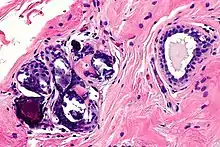

Oncology safety

The homing effect may have advantages in increasing the long-term survival of transferred fat, but concerns remain for patients with post-oncologic history, specifically breast cancer. It is more alarming since breast tumors are closely located with adipose tissue, as they develop a favorable microenvironment for cancer progression through homing and migration.[18] There are cancer-associated adipocytes (CAAs) crucial for metastasis and the progression of tumors. Under normal conditions, the adipocytes are mature and they do not differentiate. However, when ADSCs migrate and circulate in blood vessels by homing properties can result in the progression of tumor growth. Furthermore, the properties of migratory cells also promote tumor growth by secretion of trophic factors such as adipokines, including FGF, ILs and IGF-binding proteins. This increases vascularisation as such oncogenic properties are unusual for other BM-MSCs or lung-derived MSDCs.[19]